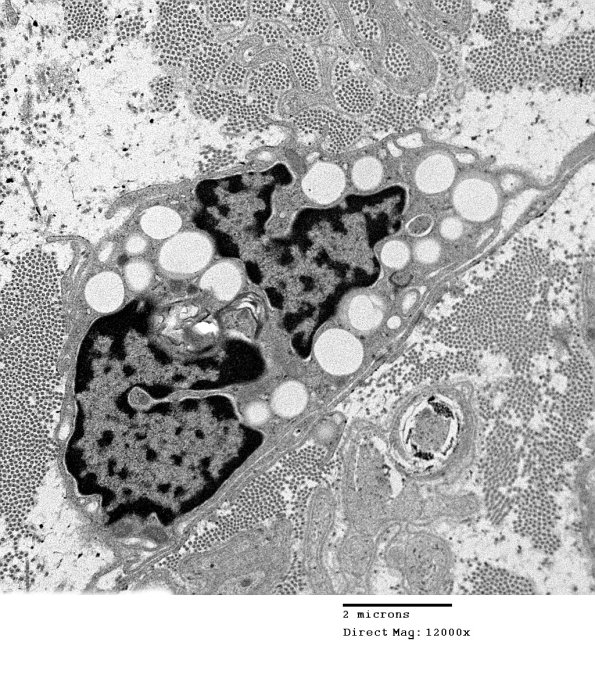

A macrophage in a sea of collagen, collagen pockets and denervated Schwann cell processes.